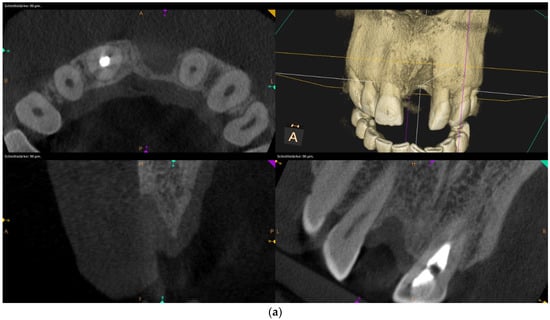

Over-contouring was defined as an over-augmentation of the alveolar process beyond the extent of the adjacent bone level (Figure 1). The reason for over-augmenting the alveolar process is often an anticipated shrinkage of the bone substitution material during the healing phase. Two patients were selected as examples to illustrate the term “over-contouring”. Patient 1 showed a Class III defect in the maxilla, and the alveolar ridge augmentation performed for correction was over-contoured (Figure 2). Patient 2 also showed a Class III defect in the maxilla, but the alveolar ridge augmentation performed for correction remained at the level of the surrounding bone (Figure 3).

Figure 3.

Clinical example of no over-contouring. (a) Class III defect with pronounced vestibular deficit and minor vertical deficit. (b) Attachment osteoplasty with a cancellous allogeneic bone block. The block fits into the contour of the surrounding alveolar process (within the envelope). The lining with the bovine granules is visible (vestibular opaque line). Cranially, the bone block ends at the bone border of the adjacent teeth.